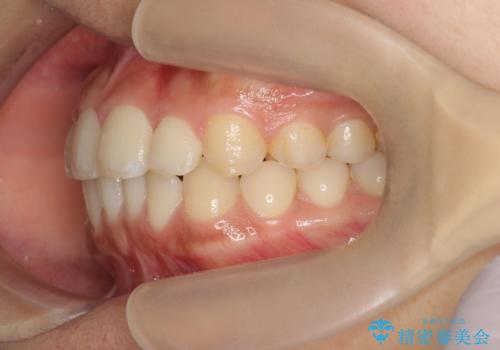

前歯のねじれ、すれ違いを改善 部分ワイヤー+マウスピース矯正

- 上下前歯のすれ違い、ねじれのある歯並びの矯正治療を求めて来院されました。

上顎前歯のみの部分ワイヤー治療を約6ヶ月行い、ねじれの問題を解決したのち、マウスピース矯正で細かな歯列を整えていきます。

前歯のすれ違いが改善することで噛みやすくなった。と矯正治療の結果に満足いただくことができました。